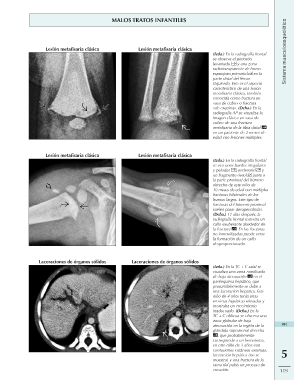

MALOS TRATOS INFANTILES Sistema musculoesquelético

Lesión metafisaria clásica Lesión metafisaria clásica (Izda.) En la radiografía frontal

Lesión metafisaria clásica se observa el periostio

Laceraciones de órganos sólidos levantado y una zona

radiotransparente de hueso

esponjoso primario en la

parte distal del fémur

izquierdo. Este es el aspecto

característico de una lesión

metafisaria clásica, también

conocida como fractura en

«asa de cubo» o fractura

«de esquina». (Dcha.) En la

radiografía AP se visualiza la

imagen clásica en «asa de

cubo» de una fractura

metafisaria de la tibia distal

en un paciente de 2 meses de

edad con lesiones múltiples.

Lesión metafisaria clásica (Izda.) En la radiografía frontal

se ven unos bordes irregulares

y peludos , esclerosis y

un fragmento óseo junto a

la parte proximal del húmero

derecho de este niño de

10 meses de edad con múltiples

fracturas bilaterales de los

huesos largos. Este tipo de

fracturas del húmero proximal

suelen pasar desapercibidas.

(Dcha.) 11 días después, la

radiografía frontal muestra un

callo exuberante alrededor de

la fractura . En las fracturas

no inmovilizadas puede verse

la formación de un callo

desproporcionado.

Laceraciones de órganos sólidos (Izda.) En la TC + C axial se

visualiza una zona ramificada

de baja atenuación en el 491

parénquima hepático, que

presumiblemente se debe a 5

una laceración hepática. Este

niño de 4 años tenía unas 119

enzimas hepáticas elevadas y

mostraba un crecimiento

inadecuado. (Dcha.) En la

TC + C oblicua se observa una

zona globular de baja

atenuación en la región de la

glándula suprarrenal derecha

, que probablemente

corresponde a un hematoma,

en este niño de 3 años con

contusiones cutáneas extensas,

laceración hepática (no se

muestra) y una fractura de la

rama del pubis en proceso de

curación.